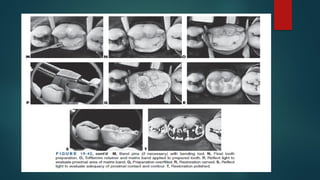

conventional latch-type contra-angle handpiece (Fig. 19-32) and TMS hand

wrenches (see Fig. 19-30).